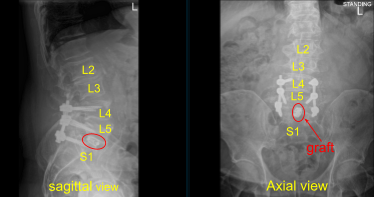

Case Study: L4-S1 Posterior Instrumented Fusion

with L5-S1 Transforaminal Lumbar Interbody fusion

with Osteotomy

The patient presented to outpatient clinic status post motor vehicle accident with signs and symptoms of lumbosacral spondylolisthesis, bilateral L5 spondylolysis, L5 compression fracture, severe compression of L5 nerve root, and clinically with foot drop, severe radiculopathy and back pain. Surgery was recommended to decompress and stabilize the lumbosacral spine.

The interspace was irrigated clear. Morselized autograft was packed in the interspace, and then a titanium 22-mm long expandable interbody spacer was gently tamped into the interspace with a mallet. AP and lateral fluoroscopy was performed to confirm midline positioning and depth; the cage was expanded to the appropriate tightness and tight.

X-rays were repeated to confirm correct positioning and size. Neuromonitoring signals were stable. Next with the left L5 pedicle completely isolated and exposed, we placed left L5 pedicle screw decorticating with electric high-speed drill cannulating with the curved freehand Lenke pedicle finder palpating for breaches using 5.0 mm tap and placing 45 mm x 6.0 diameter titanium pedicle screw without difficulty.

We then similarly placed a right L5 pedicle screw as well using similar technique. We draped the patient sterilely and obtained an intraoperative CT scan which showed correct positioning of all the pedicle screws and interbody spacer.

We took final AP and lateral x-rays, which showed correct positioning of all the hardware. The closure will be dictated separately. At the end of the case, the patient was turned supine on the cart, and transported to the recovery room in stable condition.